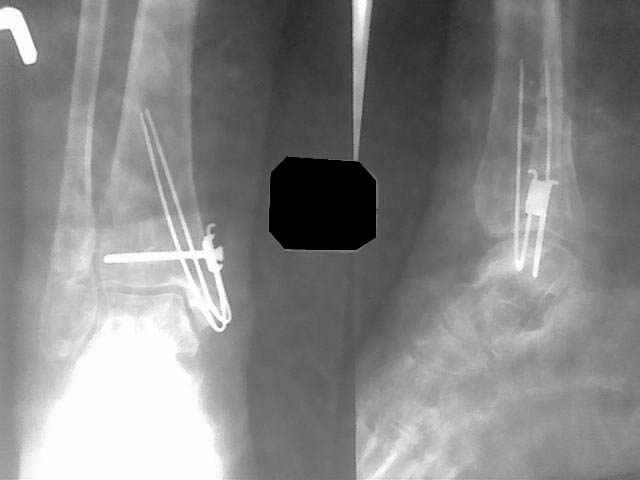

В данном случае - ложный сустав внутренней лодыжки на фоне оперативного лечения кортикальным винтом 3,5 и спицей. Часть внутренной лодыжки была лизирована. Проведена костная аутопластика. Результат налицо.

Ув. коллега. Снимки постараюсь найти, они у пациентки. Вкратце: травма 7 месяцев назад. 2х лодыжечнай перелом со смещением отломков, с подвывихом стопы. Мое мнение что синдесмоз был поврежден, хотя мнения разошлись, но позиционный винт был поставлен. Рецидивирующие свищи п/о рубцов. Металл был удален через 2 месяца. Далее больная попала ко мне с ложным суставом вн. лодыжки. Далее вы видели.